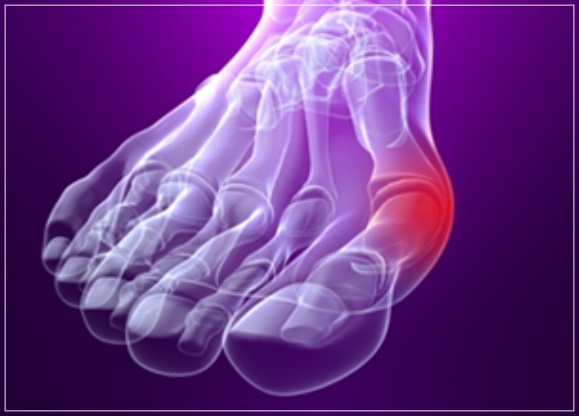

엄지 발가락의 튀어나온 관절부분(건막류)이 신발에 눌려 통증을 호소하는 것이 주 증상이나 엄지발가락이 둘째발가락 쪽으로 휘어져 있고, 관절이 안쪽으로 돌출되어 있습니다. 돌출된 관절은 서 있거나 걸을 때 자극을 받아 빨갛게 변하고 굳은살이 잡히며 염증과 통증이 발생합니다. 엄지발가락이 제 역할을 하지 못하니 발의 다른 부위에도 통증이 생기고 심해지면 발 모양의 변형, 허리의 통증 등이 발생합니다.